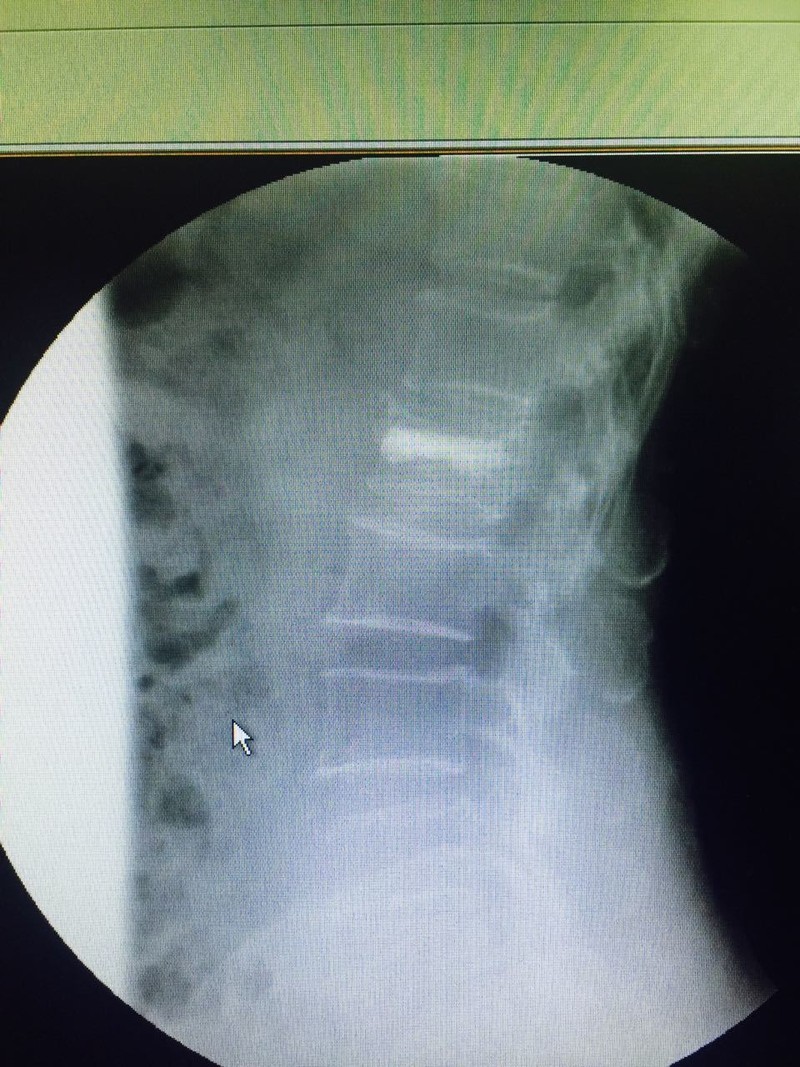

الحقن الإسمنتي للفقرات احد الحلول لعلاج الكسور المرضيه الناتجه عن هشاشة العظام

حيث حضرت مريضه٧٠ سنه تعاني من كسر انضغاطي لفقره قطنيه وبعد العرض علي د حازم

فريد جراح العمود الفقري تم عمل الفحوصات اللازمه والتي أظهرت وجود هشاشة بالعظام

وعلي الفور تم التدخل الجراحي لعمل حقن إسمنتي للفقره المنضغطه بعد رد الانضغاط وذلك من

خلال جرح صغير جدا لا يتعدي ١ سم وغادرت المريضه في نفس اليوم بعد عدة ساعات من

الجراحه وهي بحاله جيده جدا مع تحسن ملحوظ بالم الفقرات